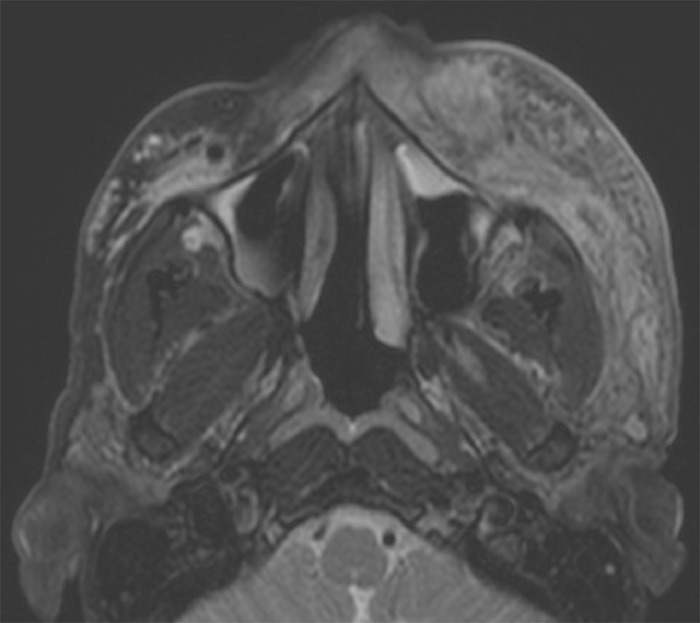

На следующий день он вернулся в отделение неотложной помощи с легким усилением отека лица и новой тошнотой и рвотой. Показатели воспаления у него были обнадеживающими, но из-за сложного клинического течения, медленного улучшения состояния и появления новых симптомов пациенту было сделано магнитно-резонансное изображение (МРТ) лица фото 2.

В дополнение к ожидаемому обнаружению целлюлита в средней части лица МРТ продемонстрировала наличие гиперинтенсивных очагов в контралатеральной средней части лица на Т2-взвешенных аксиальных срезах, предварительно подвергнутых контрастированию. После дальнейшего обсуждения с пациентом выяснилось, что за 3,5 и 2,5 года до заражения он перенес косметическую операцию по увеличению средней части лица над скулами с двух сторон с помощью Voluma. В обоих случаях ему вводили по 0,45 куб.см с каждой стороны острой иглой в трех положениях, расположенных на кости, все латеральнее средней зрачковой линии (0,1 куб. см в самом боковом месте, 0,15 куб. см в среднем месте и 0,2 куб. см в медиальном месте). Предполагалось, что отсутствие идентифицируемого наполнителя на пораженной стороне связано с изменениями целлюлита, которые превышают плотность наполнителя, поскольку пациент сообщил о симметричных инъекциях наполнителя.

У пациента, описанного здесь, наличие остаточного филлера HA было подтверждено с помощью МРТ-томографии через 2,5 года после инъекции. Внешний вид филлера, выявленного на МРТ, соответствовал описанному в литературе как гиперинтенсивный Т2. Более того, отложения филлера в контралатеральной части средней части лица не свидетельствовали об инфекции или воспалении, что позволяет предположить, что филлер все еще находится в процессе нормальной резорбции. Филлер HA может сохраняться дольше, чем положено, что сопряжено с риском отсроченных осложнений, пока остается какой-либо остаточный наполнитель.

Figure 2 -лицо, демонстрирующее целлюлит средней части лица слева и, на том же уровне, очаги гиперинтенсивности Т2 справа, соответствующие филлеру с гиалуроновой кислотой.